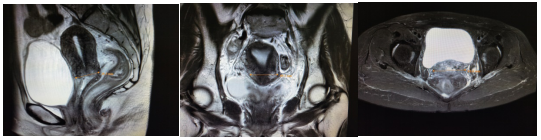

患者刘某某,女,50岁。患者4个月前无明显诱因出现阴道不规则流血,初始流血量较大,约为月经2倍,就诊于当地医院,给予对症处理后好转,故未进一步诊治。1个月前再次出现阴道流血,量多,色鲜红,就诊于当地某三甲医院,行阴道镜检查,提示宫颈局部病变恶性可能性大,遂进行病理活检,提示宫颈浸润性鳞状细胞癌,中分化。明确诊断后为求进一步治疗入我院。入院查体:外阴发育正常,已婚已产型,阴道通畅,粘膜润软,轻度充血,宫颈表面可见大小约5*4*4cm菜花样肿物,质糟脆,活动度差,触血(+),阴道前壁下1/3受累;子宫前位,大小及形态正常,活动度欠佳,无压痛;双附件区未触及明显异常,分泌物血性,量少。三合诊:双侧宫旁韧带结节样增厚,缩短明显,弹性差,达盆壁,肛门无异常,直肠粘膜光滑,指套未染血。入院盆腔核磁(图1):宫颈肿块伴宫颈积液,累及右侧输尿管并致右侧输尿管扩张积水;两侧髂血管走行区、左侧闭孔区、骶前脂肪间隙内淋巴结肿大,大部分考虑转移。结合查体及辅助检查,该患者明确诊断为宫颈恶性肿瘤(ⅢB期)。

放疗前盆腔核磁

该患者诊断明确,为中晚期宫颈癌,依据现有指南,治疗原则为同步放化疗,放疗包括外照射放疗和腔内近距离放疗。外照射放疗技术选择动态调强放疗(VMAT),盆腔淋巴结引流区剂量5040cGy/28F,阳性淋巴结剂量5992cGy/28F,同期给予铂类同步化疗,1次/周。外照射结束前1周内复查盆腔核磁(图2):宫颈肿块较前明显缩小;两侧髂血管走行区、左侧闭孔区、骶前脂肪间隙内转移淋巴结较前缩小。

外照射放后近距离放疗前盆腔核磁

腔内近距离放疗选择CT引导下宫腔管联合插植针进行,将宫腔管按照宫腔方向插入5-6cm,然后平行于阴道方向围绕宫腔管均匀布置插植针,目的将全部宫颈和宫旁组织包括在靶区范围内,从而进行病灶局部加量。近距离放疗剂量3000cGy/5F,治疗之前给予患者预防性止血、止疼等对症治疗以减轻相关副反应。患者治疗结束后1个月复查核磁(图3):宫颈局部肿块基本消失,局部呈放疗后改变,盆腔少许积液。

近距离放疗后1个月盆腔核磁